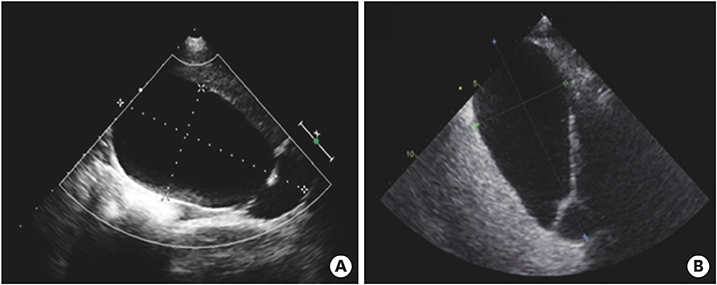

On the first day after admission, he received 2 g/kg IVIG and 50 mg/kg/day aspirin, following which his fever subsided and no further IVIG treatment was needed. His first echocardiography showed myocarditis (ejection fraction [EF], 45%) and mild ectasia of left main coronary artery (3.2–3.4 mm in diameter). On the second day after his admission, echocardiography (second follow-up) showed improved mild myocarditis (EF, 55%), improved ectasia of left main coronary artery (2.7–2.8 mm in diameter), and severe GB distension (8.9×4.6 cm in size), which possibly indicated GB hydrops (Fig. 2A). On the fourth day after his admission, although he had no fever and exhibited improvements in KD symptoms (i.e., eye injection, rash on abdomen, and cervical lymphadenopathy), he still complained of abdominal pain, distension, and tenderness of the RUQ. Follow-up laboratory findings were improved: neutrophilic leukocytosis (6,130 cells/mm3, with 33% neutrophils); decreased CRP (4.4 mg/dL), BNP (347 pg/mL), AST (40 U/L), and ALT (72 U/L); and improved hyperbilirubinemia (total bilirubin, 0.7 mg/dL). Echocardiography (third follow-up) showed normal completely improved carditis and still severe GB distension (10.2×5.5 cm in size) (Fig. 2B). Abdominal ultrasonography (US) was performed, which showed a markedly distended GB without stone, sludge, or wall thickening as well as normal bile ducts and liver morphology, which confirmed GB hydrops (Fig. 3A). On the sixth day after his admission, although his signs of KD had nearly disappeared, he still complained of abdominal discomfort, which had been moderately improving. The second follow-up abdominal US revealed a no notable change in GB distension compared to previous sonographic findings (Fig. 3B). An abdominal computed tomography (CT) scan was also obtained to exclude other hepatobiliary abnormalities, which showed similar findings as sonography, including a marked dilatation of the GB (8.0×5.5 cm in size) without stone, sludge, or wall thickening as well as normal bile ducts and liver morphology (Fig. 4). No complications necessitating surgical intervention had occurred and he was discharged 7 days after admission with only mild tenderness on the right upper-mid quadrant.

Fig. 2

Echocardiography showed severe gallbladder distension (A) 8.9×4.6 cm in size and (B) 10.2×5.5 cm in size.